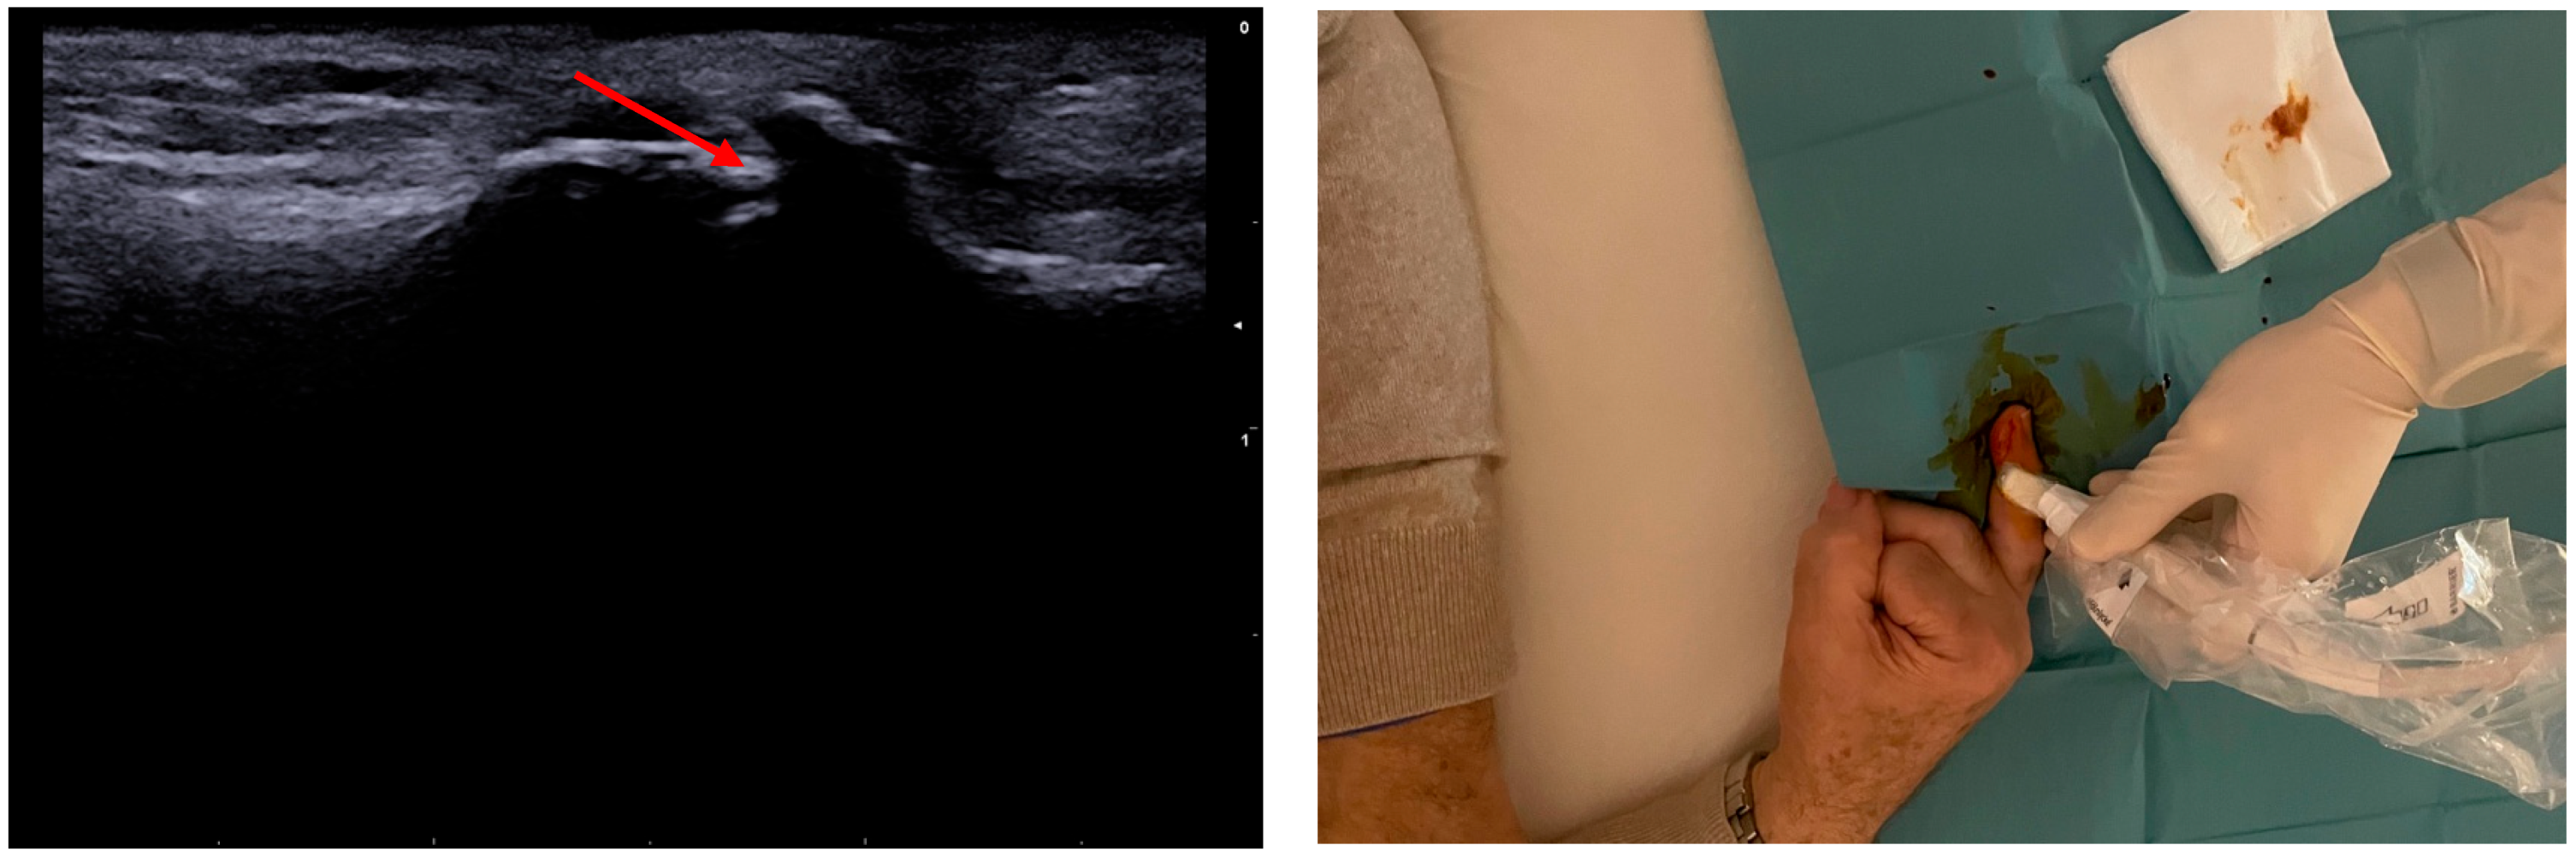

Technique Description